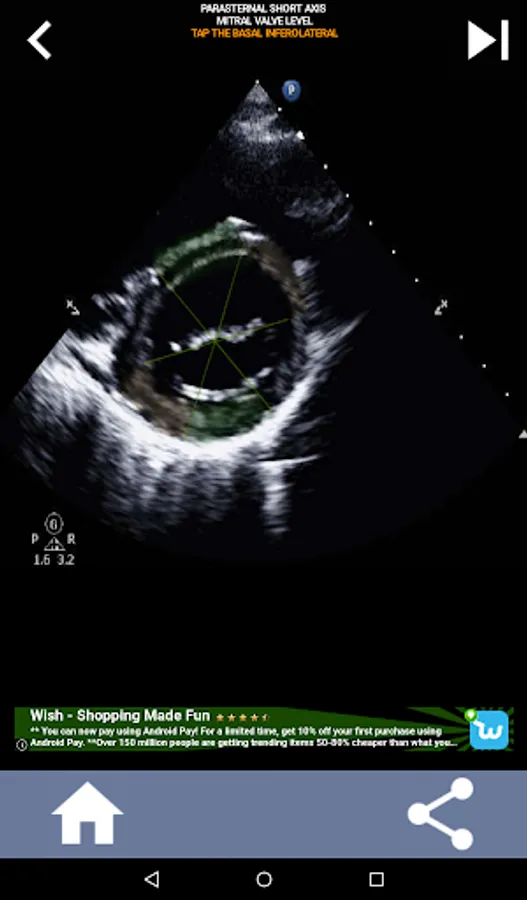

Understanding the AHA (American Heart Association) heart segments is of utmost importance for a cardiac sonographer to effectively communicate with the cardiologist who writes the report. By knowing the specific anatomical regions and their corresponding segments, the sonographer can accurately describe and communicate any abnormalities or findings, ensuring clear and concise communication between both professionals.

This understanding becomes particularly crucial when the cardiologist seeks to ascertain the precise location of a problem or when the on-call physician identifies an issue within a specific region, prompting the sonographer to accurately display the corresponding segment, such as the mid-inferior wall. Thus, possessing a comprehensive grasp of the AHA heart segments is essential skill set.

This app will test your knowlegde using actual echo images, which I often find to be the best teaching method.